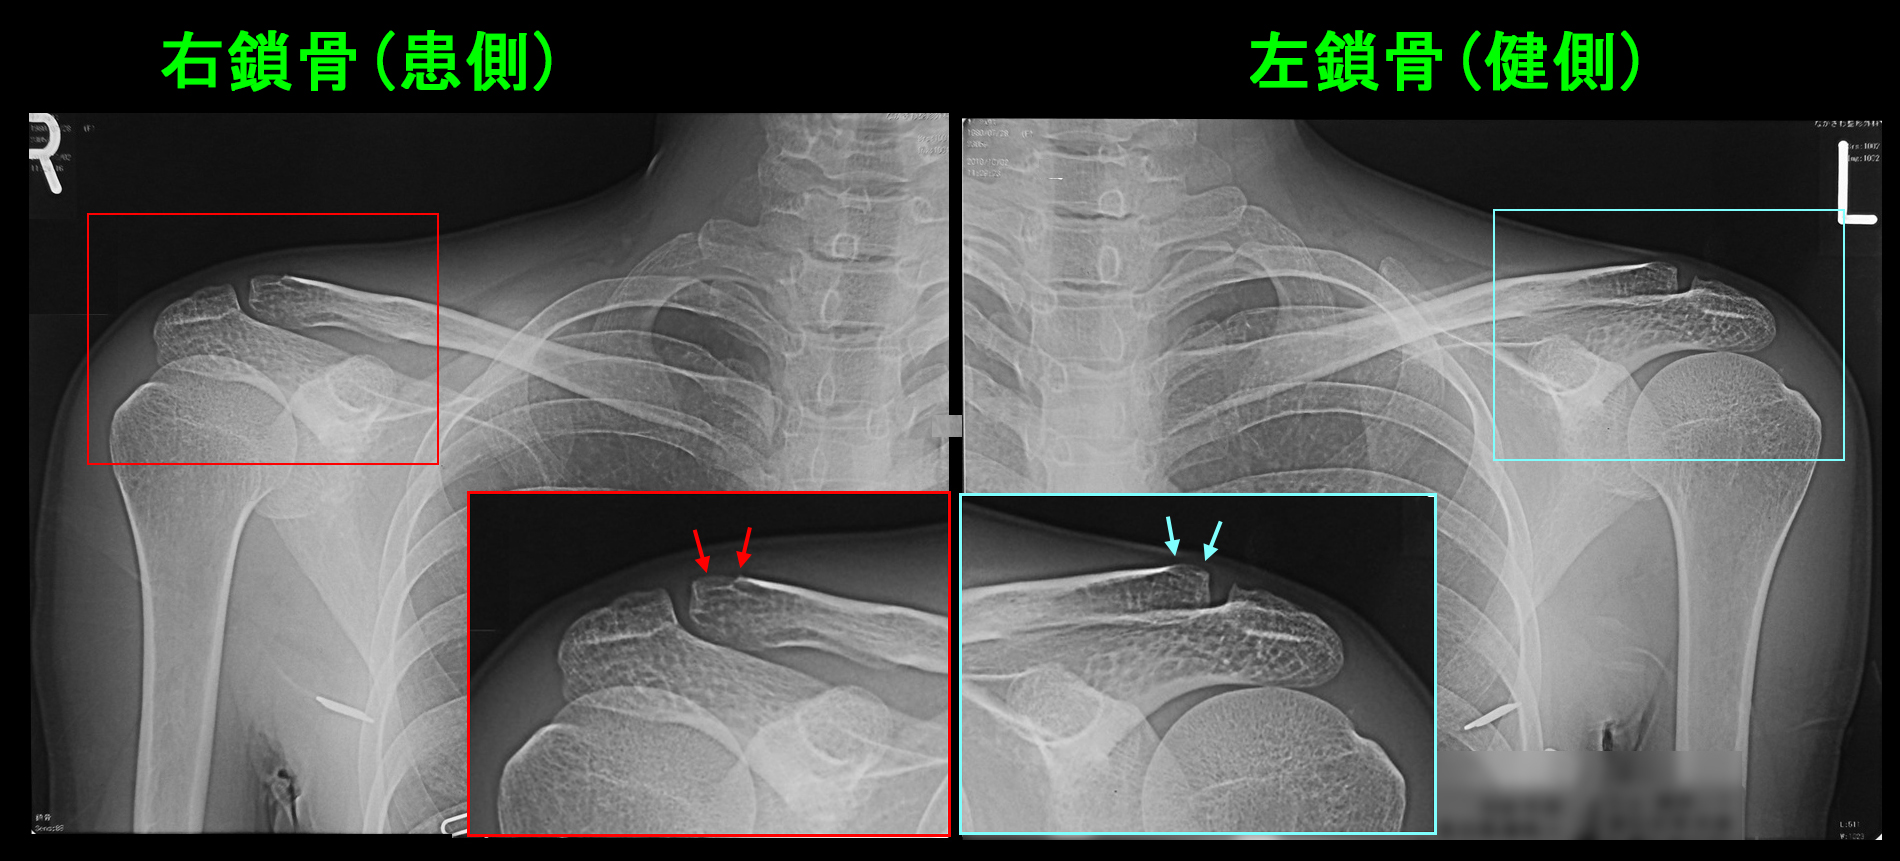

痛みは右鎖骨の外側端近傍(肩鎖関節:鎖骨と肩甲骨の接合部)の鎖骨遠位端のあたりでした。同部に圧痛(押して痛いという所見)を認めています。レントゲン像では健側の左鎖骨の遠位端部は上方に肥大しています(青矢印)。おそらく以前に打撲による小さな骨折を起こしていて、それが治る際に骨が肥大する形となったのだと思われます。右鎖骨遠位端部は赤矢印で骨の皮質(輪郭)が一部途切れています。異常所見の可能性がありますが、受傷から4か月経過しているわけで、受傷直後にはこの所見の確認は困難だった可能性が高いと思われます。肩の動きは前方からの挙上は問題ありませんでしたが、側方からの挙上は90度までの状態でした。